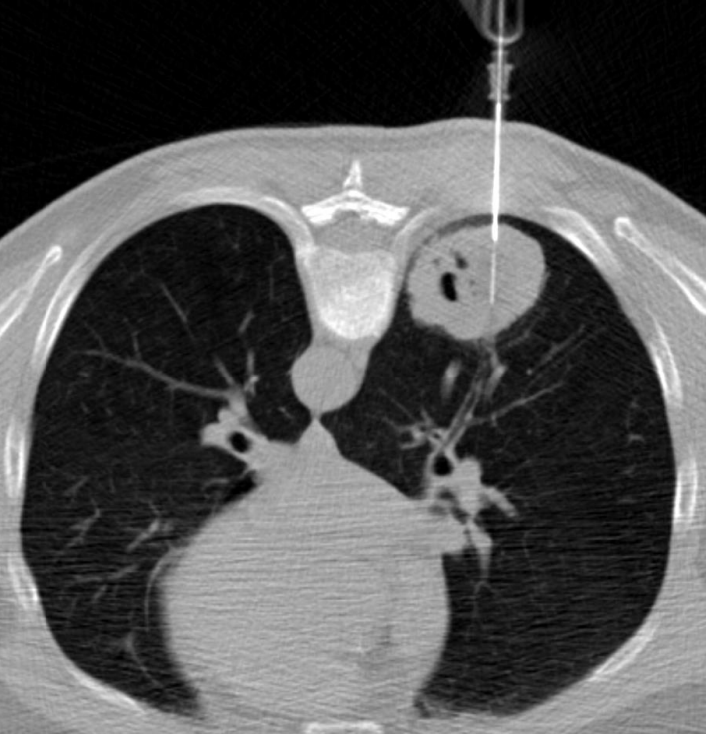

穿刺初始时,先尖刀破皮。主要是为了减少穿刺针通过皮肤的阻力,如果尽量减少破皮的深度,可以增加皮肤对导入针的支持度 然后导入针在轴向面前进1-2厘米,但始终少于皮肤到胸膜的距离。使用龙门架的激光作为引导:如果导入针和皮肤进入点都反射激光,则针位于轴向平面。 ![]() 如果引入针在没有外部支撑的情况下不能站立起来,则它没有充分地推进到胸壁肌肉。随着不断CT扫描确认,向胸膜的增量推进允许操作者调整针的轨迹以对准目标。 通过引入针给予额外的利多卡因,以减少患者的不适,特别是在前入路穿过胸肌和肋骨附近时。在穿过胸膜之前,也就是痛苦的最后一步,我们对胸内筋膜深部进行局部麻醉,如下所示: ![]() 首先,用左手的拇指和食指牢牢固定引导针,并确保在取出针芯并连接利多卡因注射器时,同一只手的至少小指保持与患者皮肤接触。在这个操作过程中,有意识地保持左手所有手指的张力,并依靠本体感觉来避免不经意地将针推进胸膜腔。 第二步,缓慢注射5-10毫升1%利多卡因。如果注射过程中没有阻力(感觉像黄油),并且成像上出现胸膜下凸起,则针尖位置正确。

在确认引入针与目标完美对齐后,在血压和呼吸频率允许的情况下,通过注射25mcg芬太尼IV来准备胸膜穿刺。然后在病人吸气时,以坚定而迅速的动作将引导针插入肺部至少2厘米。 目标是在不使用支架的情况下干净利落地刺穿胸膜,避免浅入角(30度或更小),以防止针“滑出”胸膜,从而偏离计划的轨迹。一旦穿过胸膜,针在CT引导下快速逐步向目标推进。避免在穿过胸膜后将针拉回,以减少实质出血,因为实质出血可能会掩盖小的靶目标。 将引导针推进如目标,以在取样时保持针尖固定,并尽量减少实质出血。为了尽量减少条纹伪影,可以在成像时部分撤回针芯。努力使针在肺内的时间(胸膜停留时间)最小化。 ![]() 有文献报告,同轴活检开始先使用连接注射器的22g细针进行FNAs进行细胞组织采样。为了避免在换针过程中发生空气栓塞,在取出同轴针的针芯之前,先建立盐水密封。通过千叶针的快速来回运动 (偏移5-10毫米) 获取细胞组织。在载玻片上喷两次吸入无,并将其交给现场细胞病理学专家进行快速现场评估。